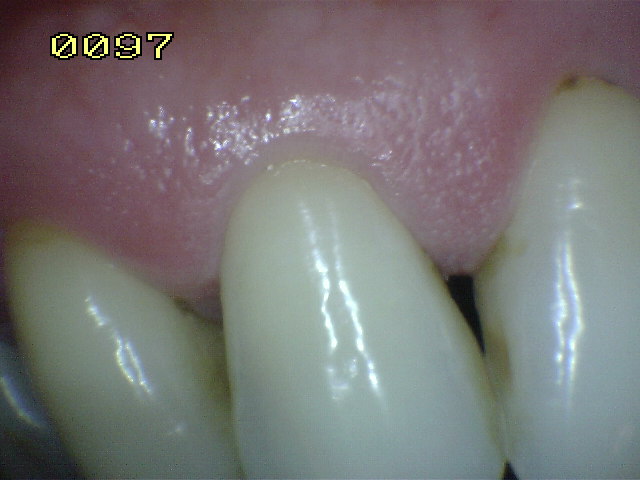

Encía Normal |

| Normal |

| Color |

Rosa pálido |

| Tamaño |

Borde cortado a filo de cuchillo |

| Aspecto |

Puntillado, tipo piel de naranja |

| Consistencia |

Firme |

| Hemorragia |

Ausente |